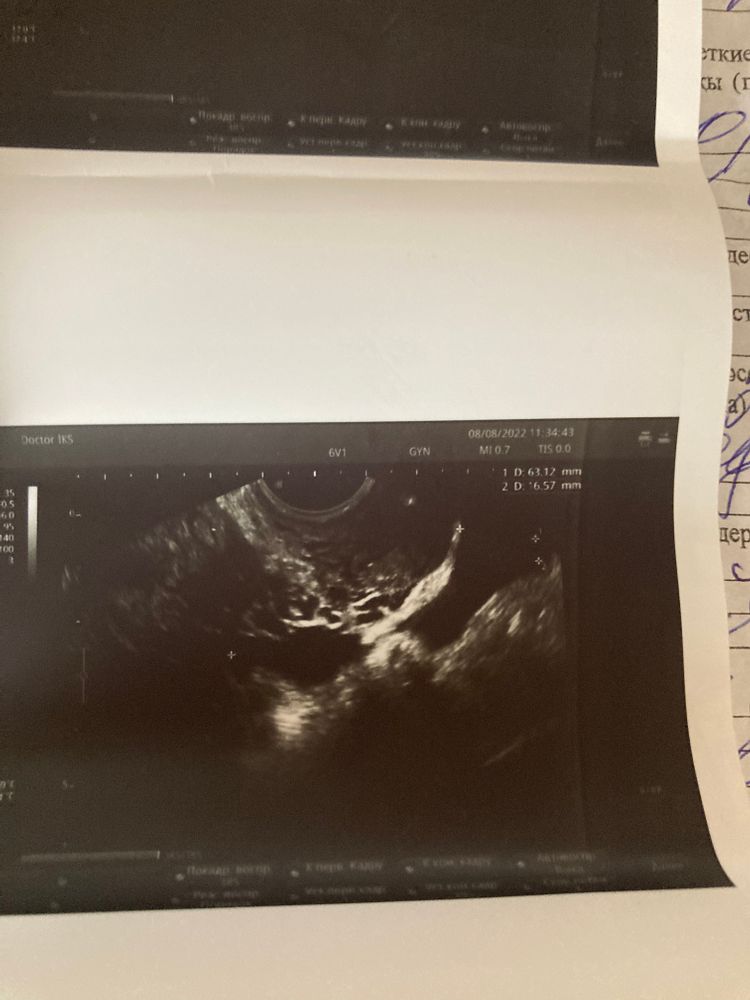

УЗИ на 19ДЦ Жидкость за маткой 3-4 дпо